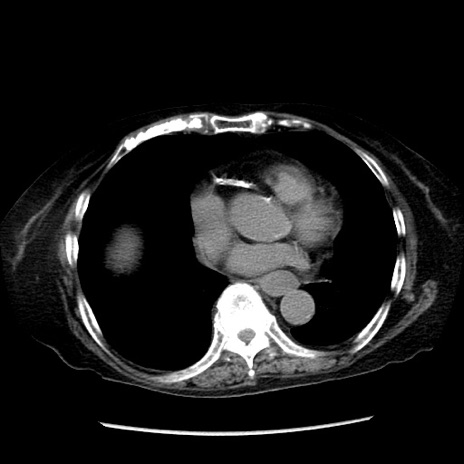

症例14(横断像)

【症例】 90歳代女性

【主訴】 腹痛・嘔吐

【現病歴】今朝から左側腹部痛を認めた。 経過観察していたが、嘔吐を認めたため来院。

【既往歴】 子宮癌術後

【身体所見】 意識清明、BP 127/54mmHg、P 98bpm Sp02 95%(RA)、BT 35.8°C、腹部平坦・軟腸ぜん動音聴取良好、右下腹部圧痛(+) 反跳痛なし

【データ】WBC 9800、CRP 0.46